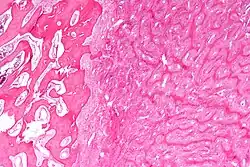

Micrograph showing fibrous dysplasia with the characteristic thin, irregular bony trabeculae and fibrotic marrow space. H&E stain. | |

Fibrous dysplasia is a mosaic disease resulting from post-zygotic activating mutations of the GNAS locus at 20q13.2-q13.3, which codes for the α subunit of the Gs G protein-coupled receptor.[13] In bone, constitutive Gsα signaling results in impaired differentiation and proliferation of bone marrow stromal cells.[14] Proliferation of these cells causes replacement of normal bone and marrow with fibrous tissue. The bony trabeculae are abnormally thin and irregular (bony spicules on biopsy).